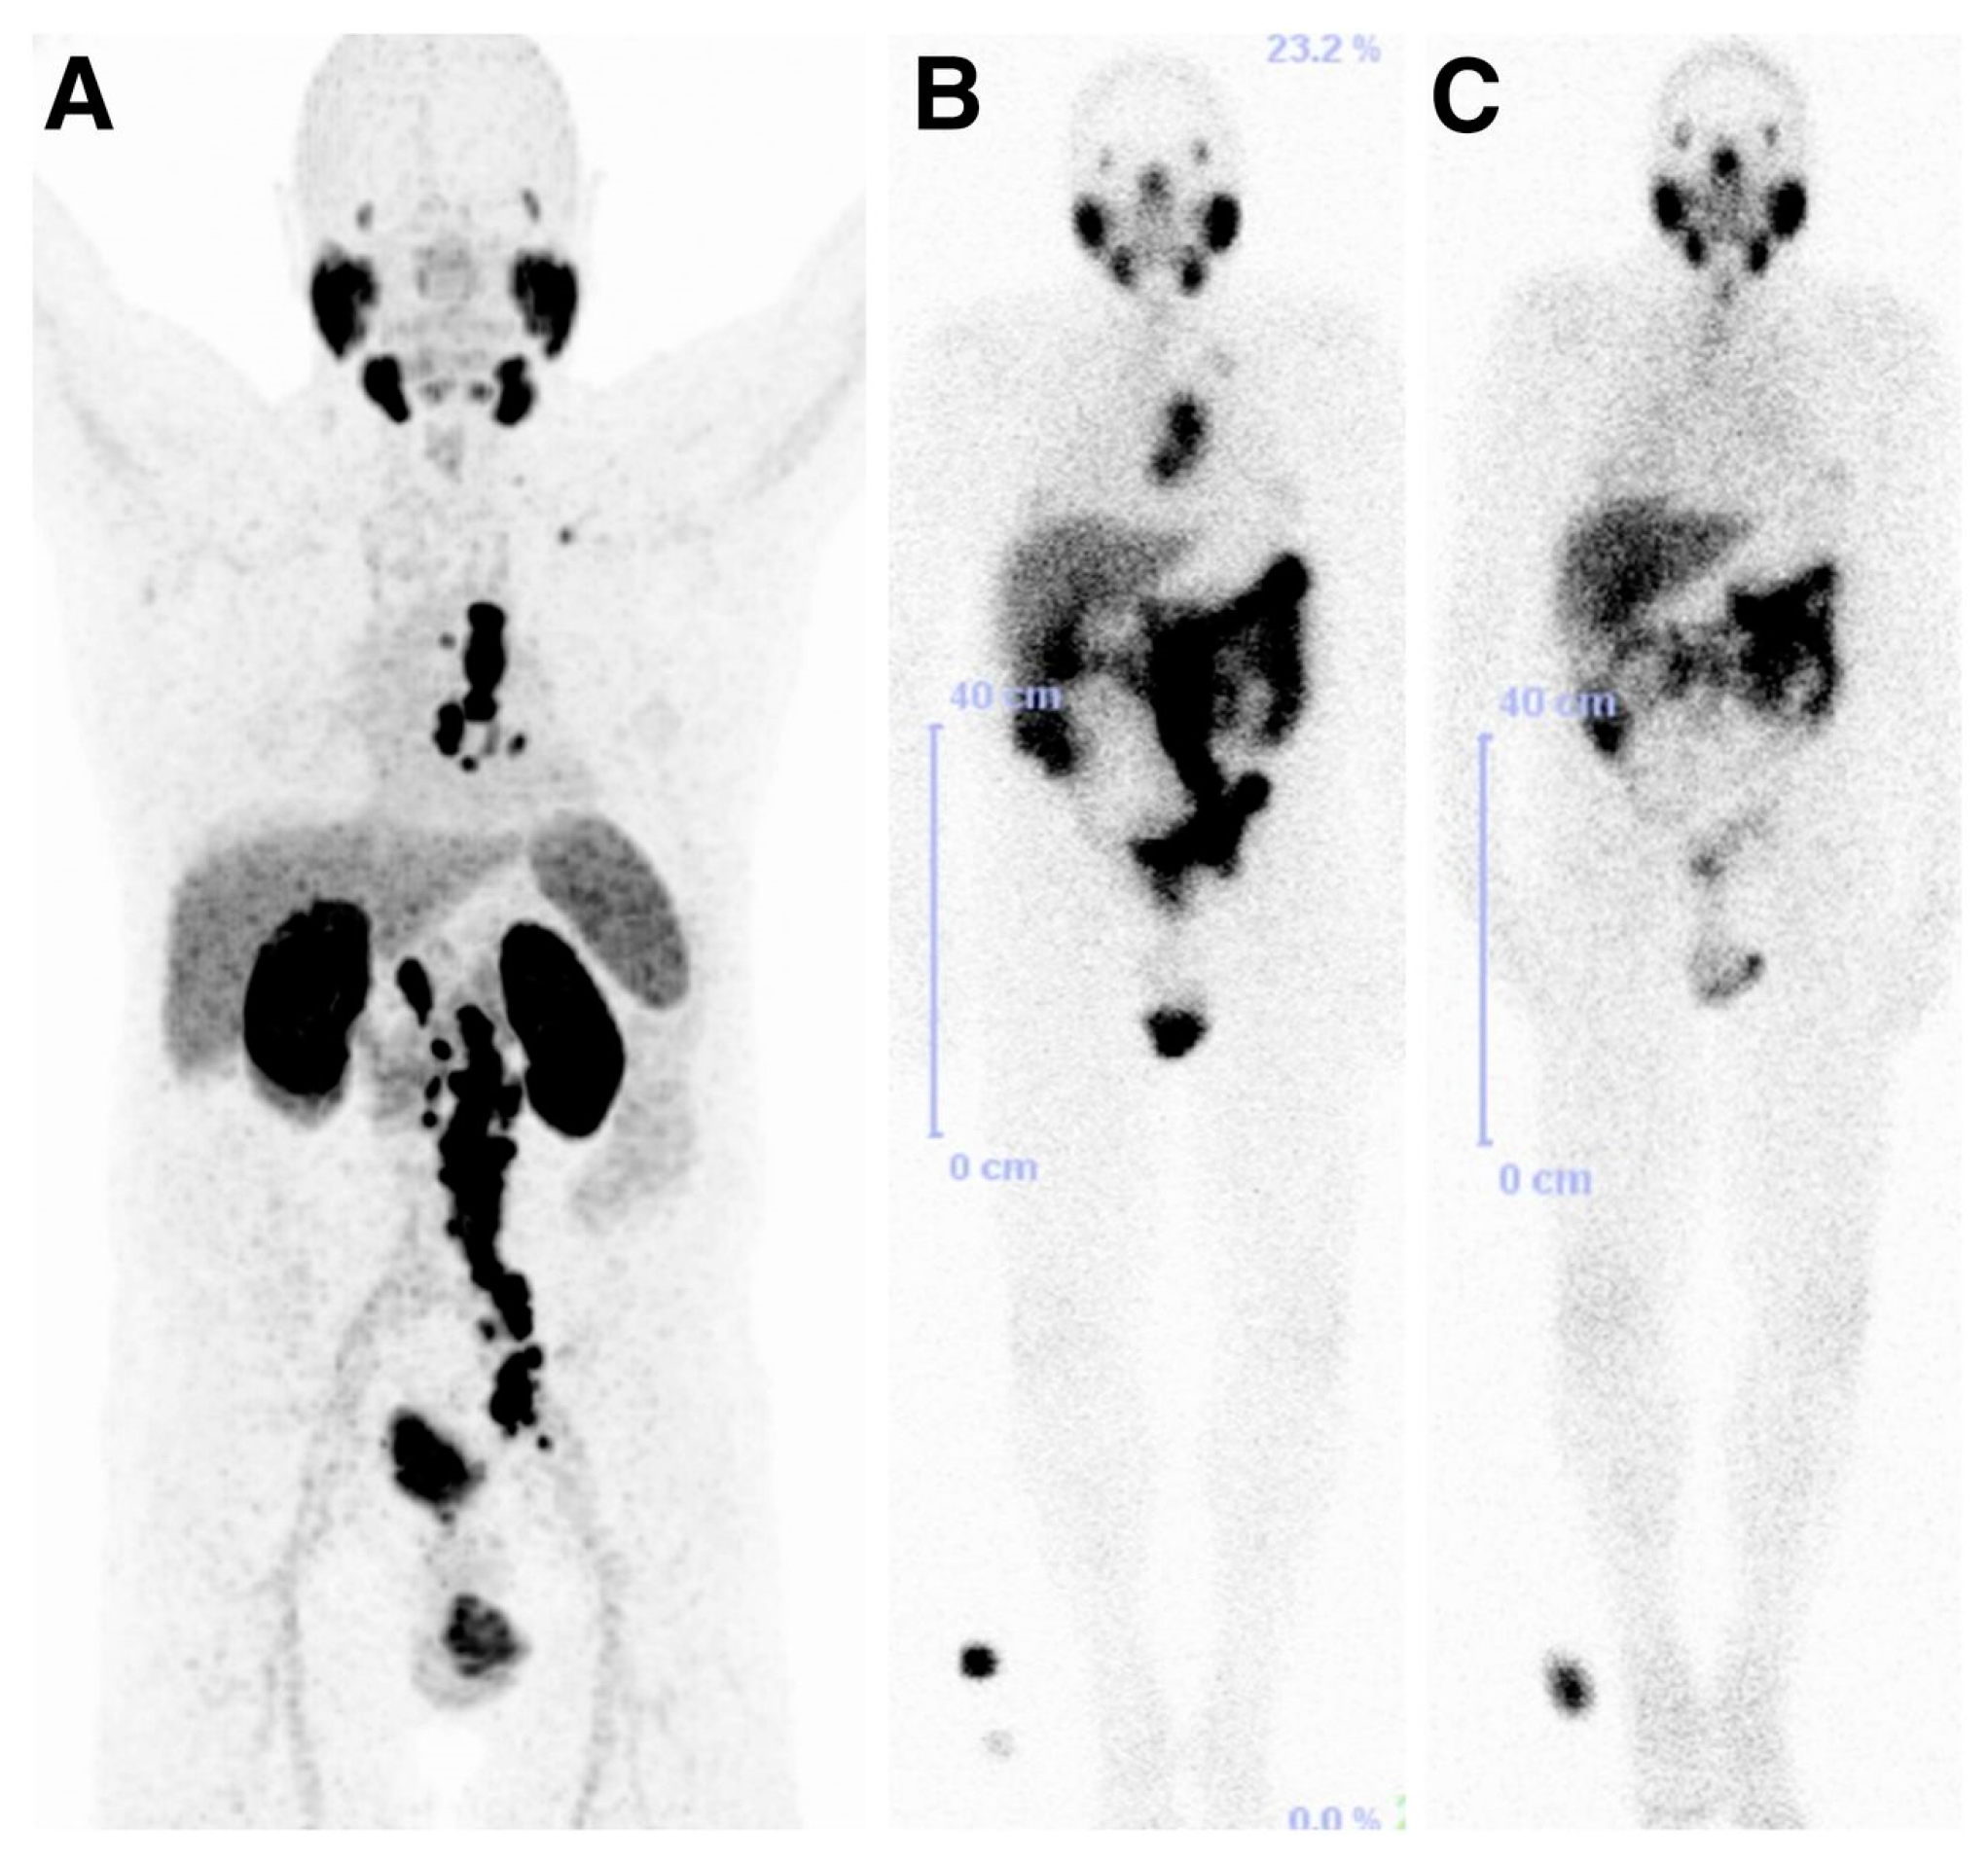

177Lu-labeled monoclonal antibody J591, which binds to the extracellular domain of PSMA, was firstly used for radionuclide therapy of prostate cancer [149]. Although the response to therapy was encouraging, the dose-limiting toxicity which is transient myelosuppression was the major reason of abandoning this therapeutic approach. In contrast, the development and preclinical evaluation of new PSMA ligands which could be labeled with therapeutic radionuclides such as 177Lu, paved the way for the reinvestigation of the 177Lu-based radionuclide therapy in patients with advanced prostate cancer. The radiotracers which have been used of the conduction of those studies are 177Lu-PSMA-617 and 177Lu-PSMA I&T (Figure 21). The clinical trials reported so far demonstrate promising results [150,151,152,153,154,155,156] with a mean tumor dose 6 to 12 fold higher compared to other critical organs such as kidneys and salivary glands. The PSA levels were found to be reduced in 60–90% of the patients after a single dose of both 177Lu-labeled PSMA-based radiotracers. The patients tolerated the therapy well, with no significant nephrotoxicity and just rarely occurring other severe side effects were observed. Although PSMA-directed radionuclide therapy bears a potential for implementation in routine clinical practice, the limited number of studies so far requires further controlled clinical trials for the establishment of the clinical value of 177Lu-PSMA-617 and 177Lu-PSMA I&T. 177Lu-PSMA-617 recently received FDA approval for phase II clinical trials in the U.S., (“First U.S. multi-center investigational clinical trial of 177Lu-PSMA-617 targeted radioligand therapy in metastatic castration resistant prostate cancer receives FDA clearance”. Daily Tribune, SyndiGate Media Inc. (Houston, TX, USA); 7 February, 2017, as found on http://www.pharmacychoice.com/News/article.cfm?Article_ID= 1690538).

Figure 21.

70-year-old patient with PSMA-avid lymph node metastases on 68Ga-PSMA PET/CT before therapy (A) and on 177Lu-PSMA I&T scintigraphy after first PSMA radionuclide therapy (B); with remarkable reduction in uptake after second PSMA RLT (C). Results were consistent with excellent therapy response projection (Reprinted with permission of [153]).